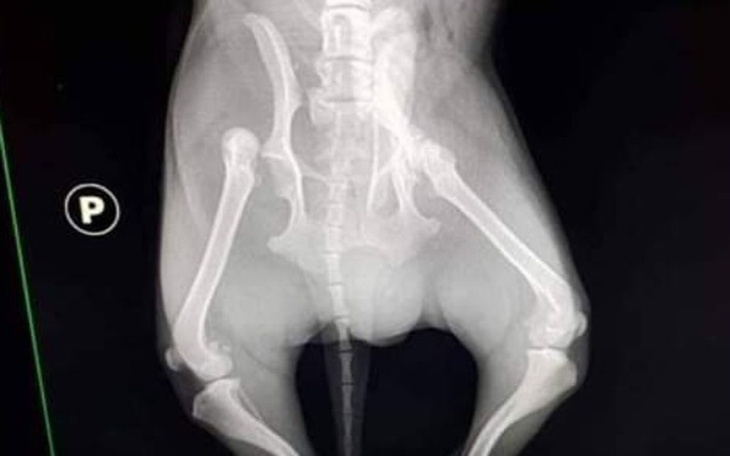

Jestem prezesem Pionkowskiego Towarzystwa Opieki nad Zwierzętami. Zwracam się z prośbą do Was , Kochani , z prośbą o ratowanie 2 letniego , psiego życia ! Mały Pikolo został znaleziony w rowie , na wsi , pod Pionkami, gdzie w bólu czekał na śmierć . Konającego pieska przywieziono do lecznicy. Lekarze stwierdzili wyziębienie, wstrząs i a w obrazie RTG złamania miednicy, stawu biodrowego i nogi tylnej. Bez skomplikowanej operacji ortopedycznej do końca życia będzie cierpiał ! Sama operacja to 2200 zł , do tego leczenie i rehabilitacja ! Gmina , która powinna to zapłacić nie ma pieniędzy . Rozważana była eutanazja ! Kiedy lekarze zapytali nas , czy pomożemy zebrać pieniądze dla malutkiego kundelka , narada była krótka : brak pieniędzy nie może skazać Pikola na śmierć lub trwałe kalectwo ! Będziemy dotąd prosić i błagać aż zbierzemy sumę potrzebną na operację i leczenie tego . Pomoc dla tego maleństwa to teraz nasz priorytet . Operacja odbyła się 22 listopada 2018 roku i trwała 6 godzin. Pikolo jest hospitalizowany w przychodni PulSvet w Pionkach , gdzie codziennie go odwiedzamy . Piesek jest ulubieńcem personelu , jest chwalony za spokój , "dobrą współpracę " w czasie zabiegów , wspaniały apetyt i wolę życia . Pomóżcie , proszę , doprowadzić go do całkowitego wyleczenia , by mógł biegać i dokazywać , jak każdy piesek >.

Zakres operacji , jaką wykonano u Pikolo.